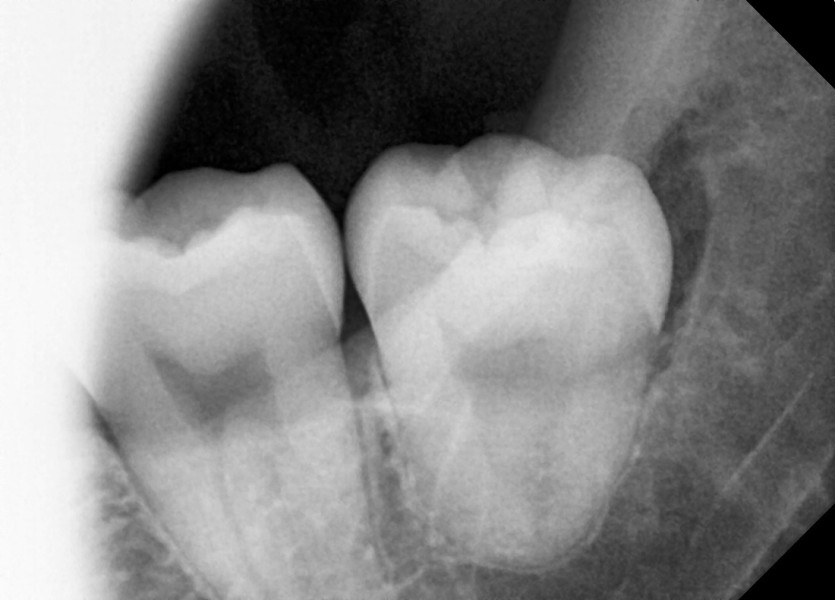

#38,48 사랑니 발치

구강 외과 전문의가 당일 발치했습니다.